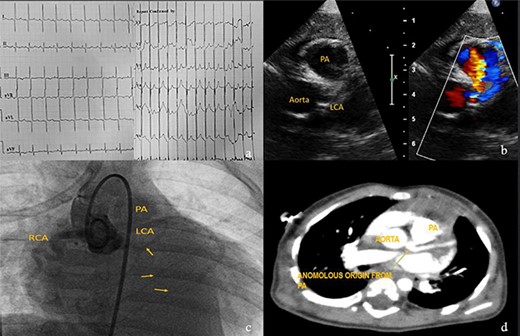

Case 4

Eight-month-male child admitted at a pediatric hospital for pneumonia and was referred to our pediatric cardiologist for cardiomegaly in his chest X-ray. ECG showed characteristic deep ‘q’ waves in Leads I, aVL, V5–V6 suggestive of anterolateral ischemia. Diagnosis of ALCAPA was suspected on echocardiography and confirmed on CT and root angiogram. His CT showed anomalous origin of left coronary from posterior sinus of PA and the aortic root angiogram spectacularly revealed retrograde flow from RCA to left system draining into the PA, as shown in Fig. 5. With only an ejection fraction (EF) of 20% due to coronary steal, child was scheduled for surgery at an earliest date possible following resolution of pneumonia. He underwent Modified Takeuchi repair with autologous pericardium used for creation of intrapulmonary tunnel with augmentation of PA. LV was noted to be stiff intraoperatively. First POD echo showed severe LV systolic dysfunction and severe MR. On second day, his blood pressure dropped requiring escalation of ionotropes. Veno-arterial extracorporeal membrane oxygenation (ECMO) support via central cannulation started, which improved his hemodynamics. Although successfully taken off the ECMO support on fifth POD, he developed sepsis and despite aggressive treatment with appropriate antibiotics, he developed multi organ dysfunction syndrome and succumbed on 16th POD.

Investigations for diagnosis of ALCAPA. (a) ECG showing characteristic findings. (b) Echocardiography. (c) Aortic root angiogram showing coronary draining into PA. (d) CT angiogram.